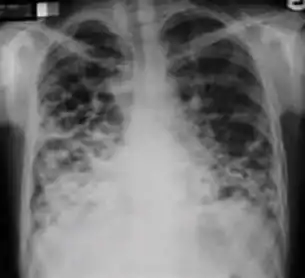

3. Nodule with poorly defined margins - Round density within the lung parenchyma, also called a tuberculoma. Nodules included in this category are those with margins that are indistinct or poorly defined (tree-in-bud sign[3]). The surrounding haziness can be either subtle or readily apparent and suggests coexisting airspace consolidation.

Chest x-ray showing nodule with margins that are indistinct or poorly defined (tree-in-bud sign) in post-primary pulmonary TB.